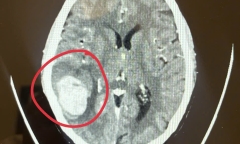

Cứu sống ngoạn mục nam bệnh nhân bị tắc thân nền, loại đột quỵ có tỷ lệ tử vong trên 90% sau bữa nhậu.